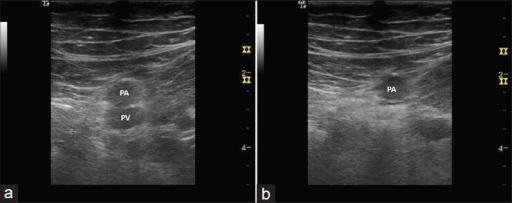

Normal

Abnormal

- Arteries are the thick walled and more circular vessels identified

- Noncompressible vein may be mistaken for an artery, leading to a false negative result

- An artery may be mistaken for a non-compressible vein, leading to a false positive result